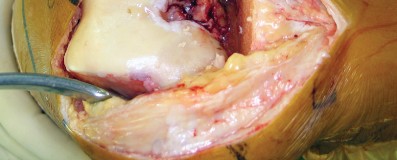

تتغطى أسطح هذه العظام بغضروف ناعم يسمح لها بالانزلاق بسلاسة فوق بعضها البعض. كما يحتوي المفصل على أربطة قوية تثبت العظام معًا وتوفر الاستقرار، وأوتار تربط العضلات بالعظام، بما في ذلك الوتر الرضفي ووتر العضلة الرباعية. تحيط بالمفصل محفظة مفصلية تحتوي على سائل زليلي يقلل الاحتكاك.

كيف يؤثر التدخل الجراحي المحدود على الأنسجة

الحفاظ على العضلة الرباعية:

وهي العضلة الرئيسية المسؤولة عن تمديد الركبة. يقلل هذا النهج من قطع هذه العضلة أو فصلها، مما يؤدي إلى تعافٍ أسرع لقوتها ووظيفتها.

تقليل تضرر الأنسجة الرخوة:

عن طريق العمل من خلال "نافذة" جراحية أصغر، يتم تقليل التلاعب بالأنسجة والأربطة المحيطة، مما يقلل من النزيف والتورم والألم بعد الجراحة.

هذا الحفاظ على الأنسجة هو المفتاح وراء الفوائد التي يقدمها استبدال مفصل الركبة بالحد الأدنى من التدخل الجراحي، ويحرص الأستاذ الدكتور محمد هطيف على تطبيق هذه المبادئ بدقة لتعظيم فوائدها لمرضاه.